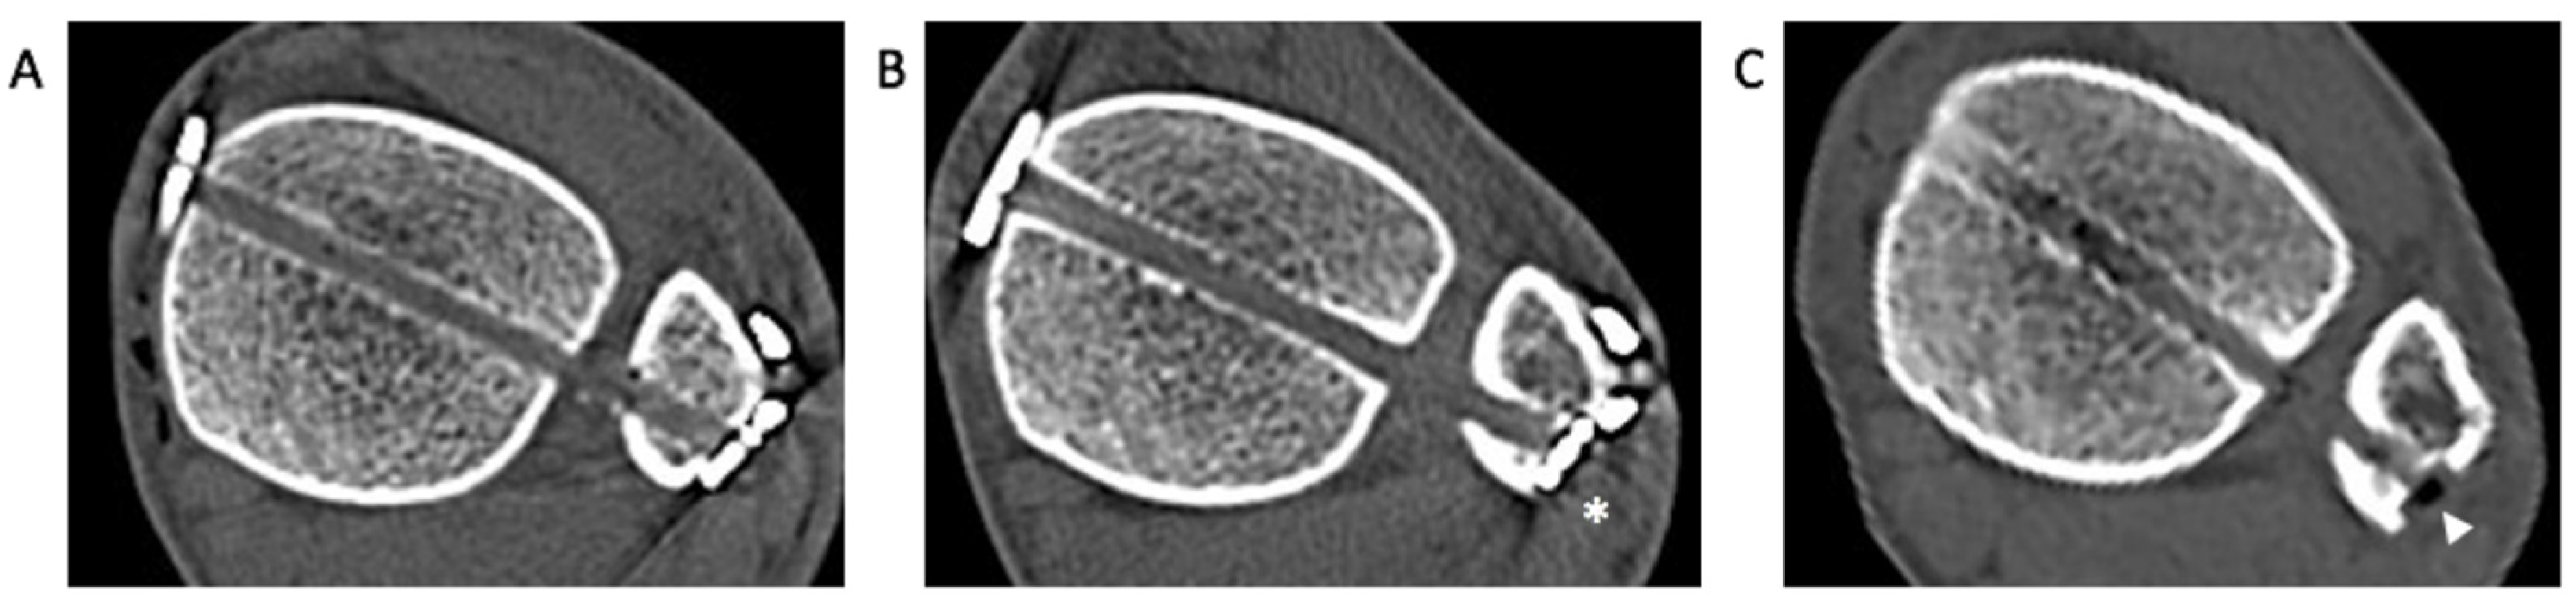

2.6. Computed Tomography (CT) Analysis